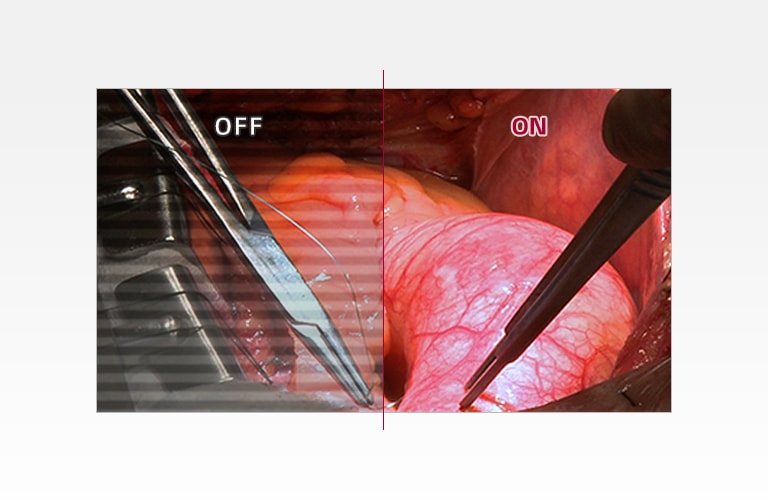

10 bittiä / sRGB 115% (syvä punainen)